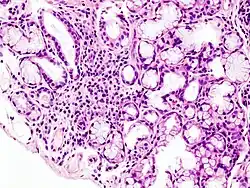

Image with a microscope of focal lymphoid infiltration in the minor salivary gland associated with Sjögren's disease

A lip/salivary gland biopsy takes a tissue sample that can reveal lymphocytes clustered around salivary glands, and damage to these glands from inflammation. This test involves removing a sample of tissue from a person's inner lip/salivary gland and examining it under a microscope. On such biopsies, the single most important test result in the diagnosis of the oral component of Sjögren syndrome is likely the focus score, which is the number of mononuclear cell infiltrates containing at least 50 inflammatory cells in a 4 mm2 glandular section.[66] The Chisholm-Mason grades are also widely used for salivary gland biopsies (see table).[67]